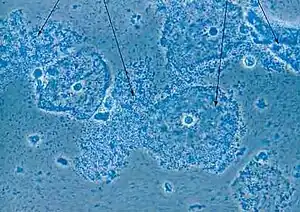

| Micrograph of bacterial vaginosis — cells of the cervix covered with rod-shaped bacteria, Gardnerella vaginalis (arrows). | |

- The presence of clue cells on wet mount. Similar to the whiff test, the test for clue cells is performed by placing a drop of sodium chloride solution on a slide containing vaginal discharge. If present, clue cells can be visualized under a microscope. They are so-named because they give a clue to the reason behind the discharge. These are epithelial cells that are coated with bacteria.

- Clue cells on microscopy

An alternative is to use a Gram-stained vaginal smear, with the Hay/Ison[35] criteria or the Nugent[23] criteria. The Hay/Ison criteria are defined as follows:[34]

- Grade 1 (Normal): Lactobacillus morphotypes predominate.

- Grade 2 (Intermediate): Some lactobacilli present, but Gardnerella or Mobiluncus morphotypes also present.

- Grade 3 (Bacterial Vaginosis): Predominantly Gardnerella and/or Mobiluncus morphotypes. Few or absent lactobacilli. (Hay et al., 1994)

Gardnerella vaginalis is the main culprit in BV. Gardnerella vaginalis is a short rod (coccobacillus). Hence, the presence of clue cells and gram variable coccobacilli are indicative or diagnostic of bacterial vaginosis.

Nugent score

The Nugent Score is now rarely used by physicians due to the time it takes to read the slides and requires the use of a trained microscopist.[4] A score of 0-10 is generated from combining three other scores. The scores are as follows:

At least 10–20 high power (1000× oil immersion) fields are counted and an average determined.